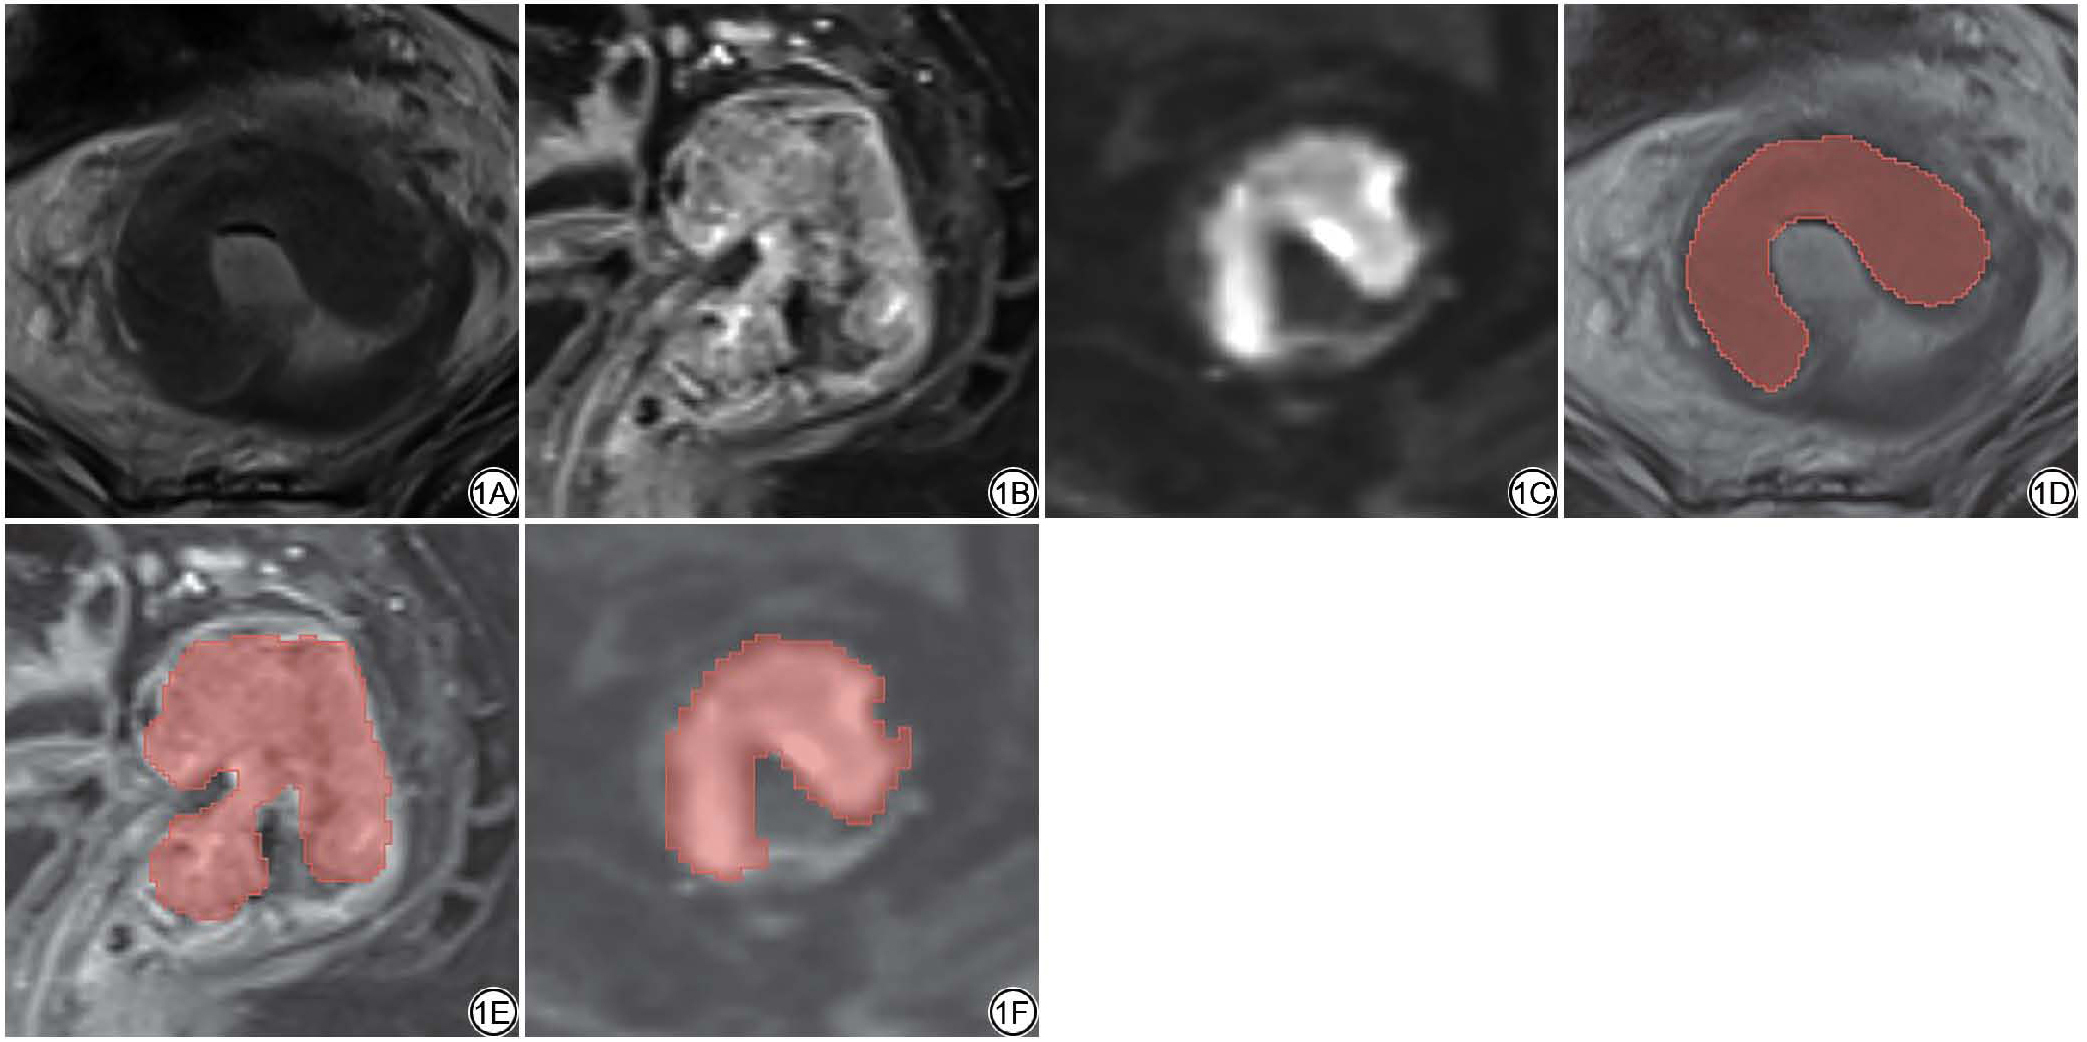

将高分辨率轴位T2WI、轴位DWI及矢状位CE-T1WI序列以DICOM格式导入ITK-SNAP软件(版本4.2.0,美国宾夕法尼亚大学PICSL实验室与犹他大学SCI研究所,http://www.itksnap.org)。由两名分别具有8年及10年胃肠肿瘤诊断经验的放射科主治医师在未知病理结果的情况下独立完成ROI分割。分割过程中,通过调整MRI图像的窗宽与窗位,并综合参考轴位、冠状位及矢状位多个序列,以准确界定肿瘤边界。两位医师使用该软件在每一层MRI图像上沿病灶边缘手动逐层勾画ROI,过程中注意避开肠腔气体、直肠系膜及正常肠壁等非目标组织(图1)。随后,ITK-SNAP将逐层勾画的二维区域整合为完整的三维体素级ROI。

图1  使用ITK-SNAP在T2WI、CE-T1WI、DWI(b=800 s/mm2)序列上勾画感兴趣区(ROI)示意图。1A~1C:T2WI、CE-T1WI、DWI图像;1D~1F:已勾画ROI的T2WI、CE-T1WI、DWI图像。CE-T1WI:对比增强T1WI;DWI:弥散加权成像。